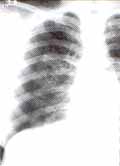

Fig 4: Neumotórax a tensión izquierdo.

Diagnóstico de neumotórax a tensión

Un neumotórax a tensión se diagnostica cuando hay desviación importante del mediastino hacia el lado contralateral e inversión del diafragma en el mismo lado. En estos casos la presión intrapleural espiratoria excede la presión atmosférica.